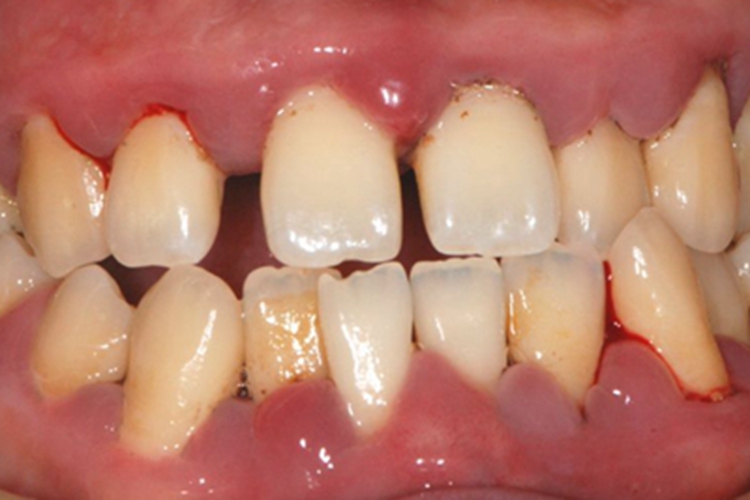

急性坏死性龈口炎多见于儿童,早期牙龈边缘及龈乳头红肿、充血,呈小疙瘩样改变,表面凹凸不平,部分肿胀严重充斥牙缝,患处牙龈易出血,疼痛明显,口内有特殊的坏死性口臭。

急性坏死性龈口炎是由梭杆菌和螺旋体感染引起,发生在牙龈边缘的急性坏死性口腔疾病。正常情况下,梭杆菌和螺旋体为口内共生菌,一般不感染致病,但在过度疲劳、营养不良引起菌群失调时可引发口腔黏膜病损。